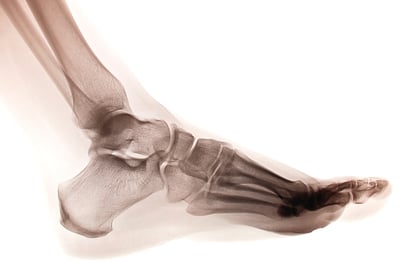

운동 훈련에 있어서는, 근력 및 컨디셔닝 코치들이 종종 발-발목 복합체를 간과하는 경우가 많다. 그러나 이를 적절히 분석하면 스포츠 경기력 향상에 활용할 수 있는 중요한 정보를 얻을 수 있다.

발 자체는 운동선수와 지면, 또는 운동 기술이 수행되는 모든 표면 사이의 인터페이스로 생각할 수 있다.

사실, 이 상호작용에서 발생하는 총 힘뿐만 아니라 이 힘이 발바닥 전체에 어떻게 분배되는지와 발 굴림의 타이밍 및 지속 시간도 중요합니다. 압력 매핑 기술의 발전으로 발을 후족부, 중족부, 전족부 및 내측과 외측으로 분할하여 평가할 수 있으며, 각 분리된 영역에 대한 힘-시간 및 압력-시간 곡선을 분석할 수 있습니다.